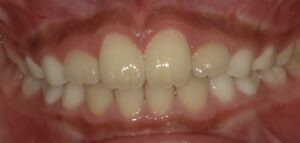

2番目の歯が前進し綺麗になっています。

軽度の叢生(そうせい 重なっていること)の場合、

プレオルソが効果を発揮することが多いです。